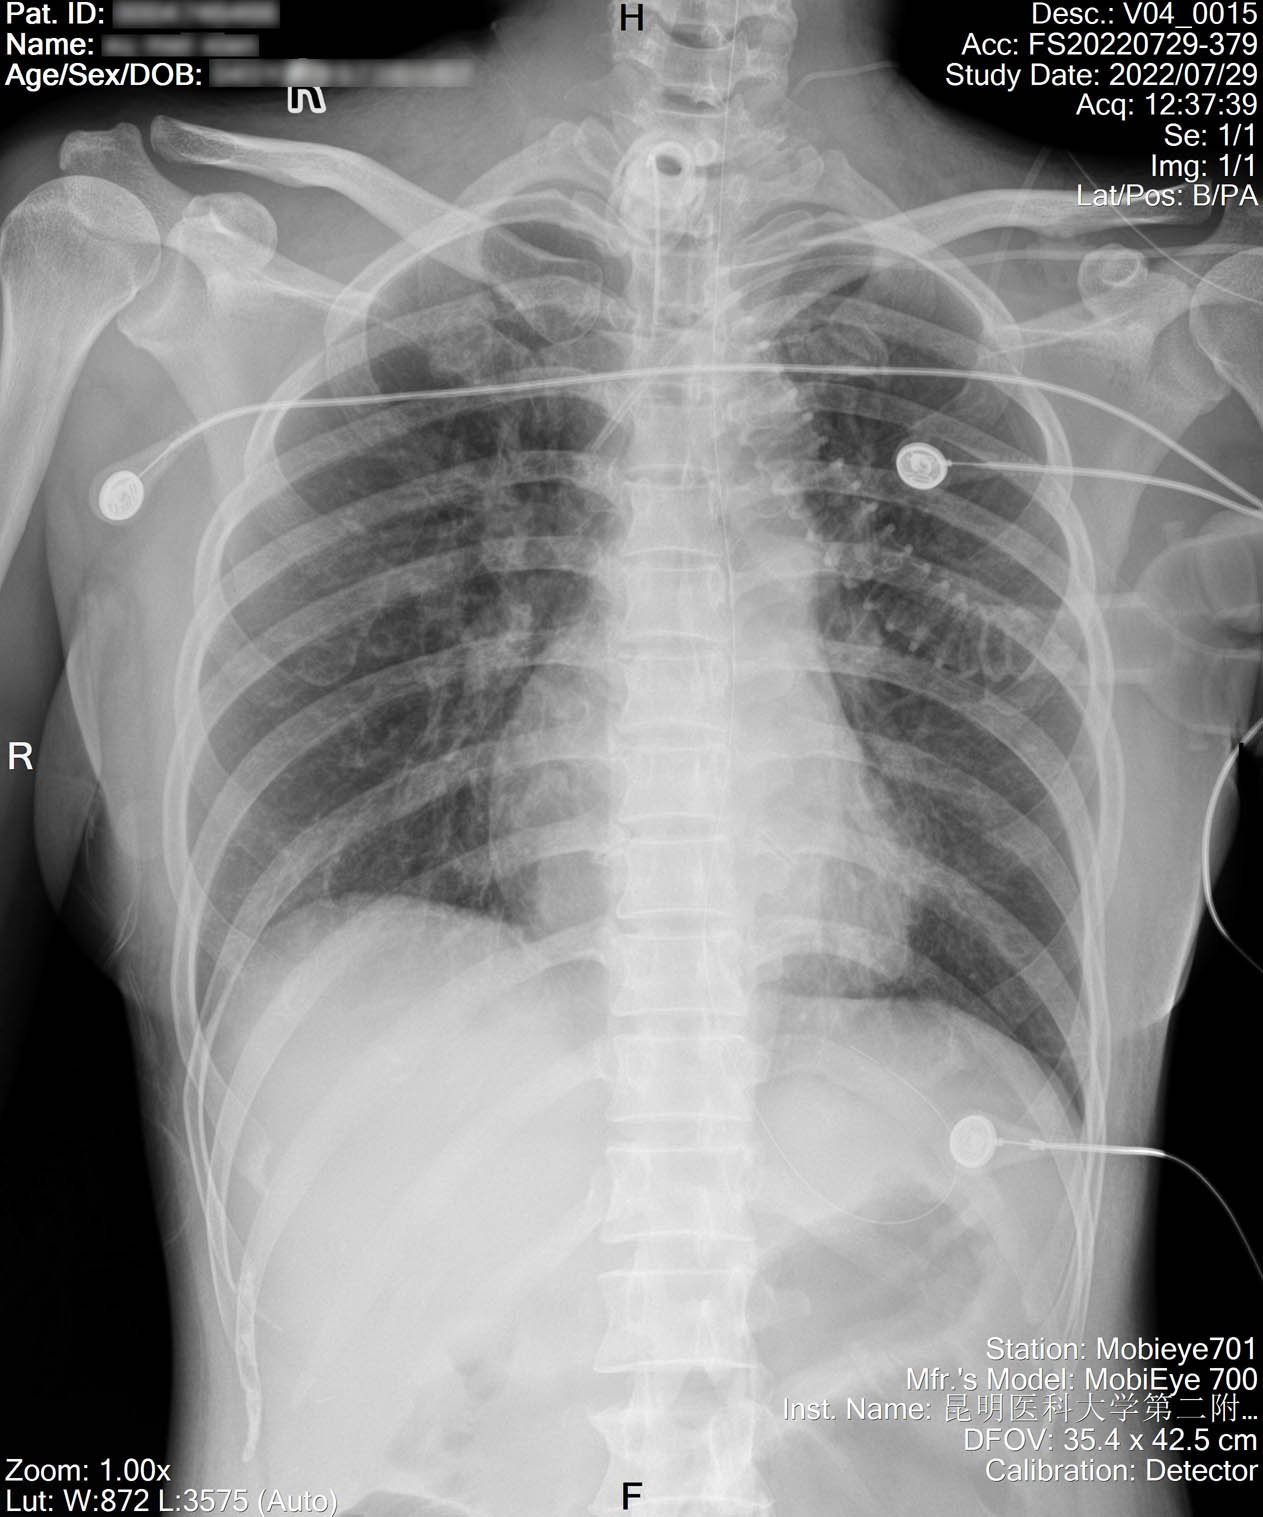

2022-07-29_胸片